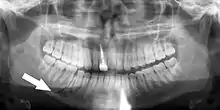

Minimally-displaced fracture in right mandibular. Arrow marks fracture, root canal on central incisor, teeth to the left of fracture do not touch

Panoramic radiograph showing Stafne defect (arrowed).